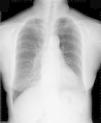

Histological examination showed the tumor to be composed of mature adipocytes, with the capsule intact. There were intervening fibrous bands, indicating this tumor to be a variant of a fibrolipoma. There was no evidence of malignancy (Fig. 5A and B). Her symptoms of dysphagia and prior unexplained sinus tachycardia improved after the operation. During a follow-up of more than 2 years, the patient has had no recurrence (Fig. 6).